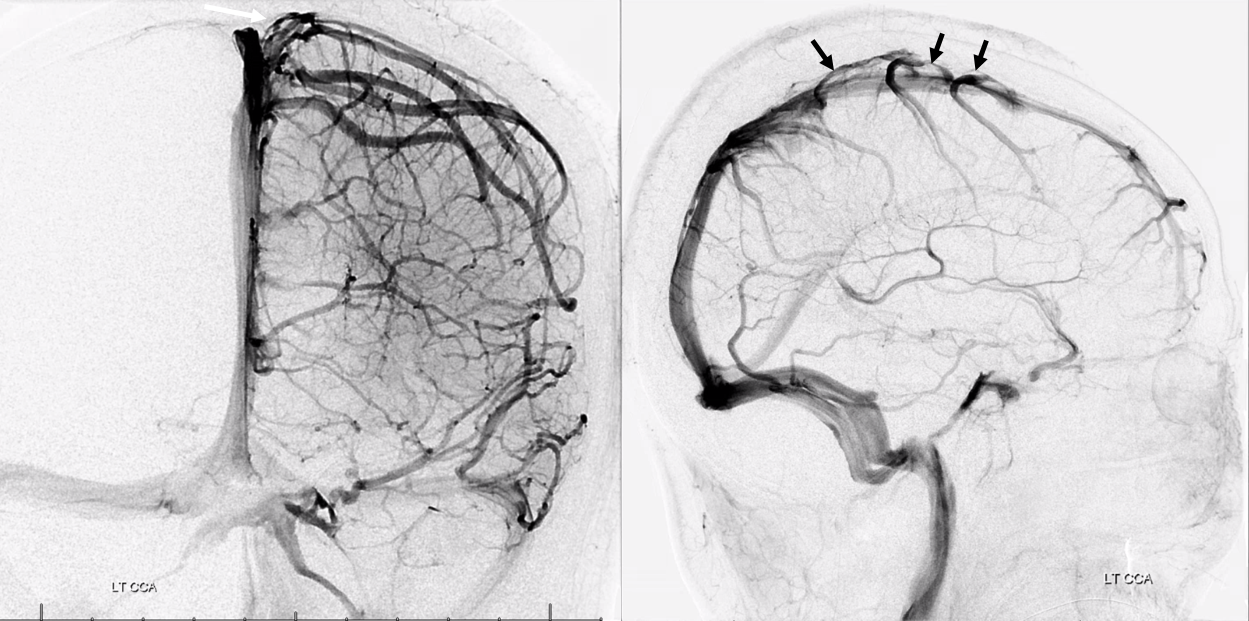

All of the above anatomic knowledge can become very useful in evaluation of venous thrombosis. Numerous collateral pathways develop in this setting attempting to compensate for the loss. The most dramatic cases usually involve the largest channel — the superior sagittal sinus. In this case, a man presented with what initially was thought to be vasculitis-related brain hemorrhage. Subsequent workup led to an angiogram, where sagittal sinus thrombosis with extensive trans-cerebral and trans-osseous emissary vein collateral channels was seen. In retrospect, these findings were present on the patient’s earlier contrast MRI. “Venovibe” or other contrast-enhanced MR venograms can very sensitive, particularly when interpreted with the appropriate index of suspicion. Noncontrast 2-D time of flight MRV I consider to be next to useless as a problem-solving technique. Any thin-slice postcontrast T1 study is vastly superior.

Angio is much easier to appreciate. It is well to learn how to spot these veins on MR or CT, as most patients don’t get presurgical angiography for nonvascular lesion

The general neurosurgical fact that the anterior third of the superior sagittal sinus can be safely sacrificed is true almost all the time. When it is not, consequences can be catastrophic. Normally, few veins drain into the anterior 3rd of the SSS, and these usually have collaterals. However, occasionally a large frontal or sylvian vein happens to drain anteriorly. Taking this sinus means risking a venous infarct. Here is an extreme example of dominant inferior left frontal vein draining into the anterior third of the frontal sinus, on MRI. Case courtesy Dr. Howard Riina